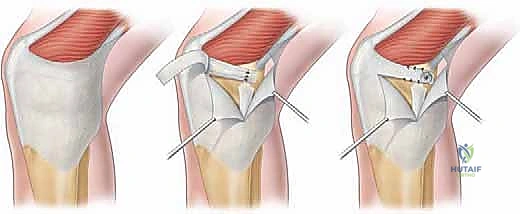

Upon reaching the superficial fascia, the surgeon develops the interval between Layer 1 and Layer 2. The fascia overlying the VMO is identified, and the distal muscular fibers are traced to their insertion on the medial patella and the underlying MPFL. The avulsed edge of the MPFL is typically identified by a localized hematoma or organized scar tissue in the subacute setting.

The retinaculum is incised longitudinally, slightly medial to the patellar border, to expose the torn edge of the ligament. The stump is carefully mobilized, freeing it from underlying capsular adhesions to ensure it can be advanced to the patellar footprint without excessive tension. The quality of the tissue is reassessed at this stage; it must be robust enough to hold high-strength suture.

Preparation of the patellar bed is a critical step for biologic healing. The native insertion site on the proximal two-thirds of the medial patellar facet is exposed. Using a curette, rongeur, or a high-speed burr, the medial cortical margin is lightly decorticated down to bleeding cancellous bone.

This bleeding bed provides the necessary marrow-derived mesenchymal stem cells and growth factors to facilitate robust ligament-to-bone healing. Two suture anchors (typically 4.75 mm or smaller, biocomposite or PEEK) double-loaded with ultra-high-molecular-weight polyethylene (UHMWPE) sutures are then placed into the decorticated patellar margin. The anchors are spaced appropriately (one proximal, one distal) to recreate the broad native footprint.

The sutures are then passed through the mobilized MPFL stump. A secure, tissue-gripping stitch configuration is mandatory to prevent pull-through. A Krackow stitch or a locking Mason-Allen configuration is placed using the limbs from both anchors, effectively grasping the robust fibrous tissue of the MPFL and the overlying VMO fascia.

The critical moment of the procedure is tensioning. The knee is placed in 30 to 40 degrees of flexion, the point at which the patella should be fully engaged within the trochlear groove. The sutures are drawn tight, advancing the MPFL stump directly onto the decorticated bleeding bone bed. The surgeon must manually assess patellar tracking and lateral translation. The goal is to restore a firm endpoint with 1 to 2 quadrants of lateral glide. Overtensioning must be strictly avoided; the MPFL is a check-rein, not a medializing tether. Once the ideal tension is achieved, the knots are tied securely. The knee is then cycled through a full range of motion to ensure the repair is isometric, does not capture the patella in extension, and maintains stability in flexion.